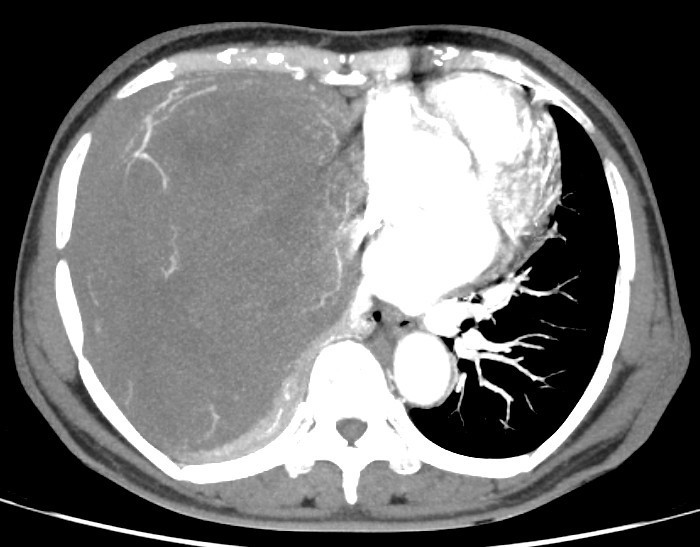

Kết quả chụp cắt lớp vi tính tại bệnh viện Ung Bướu Hà Nội cho thấy, lồng ngực phải có khối đặc kích thước 20x15 cm đè xẹp phổi, thâm nhiễm trung thất, thành ngực. Bệnh nhân được tiến hành sinh thiết khối u, kết quả giải phẫu bệnh là u xơ đơn độc.

| Hình ảnh khối u choán hết khoang lồng ngực của bệnh nhân - Ảnh BVCC |